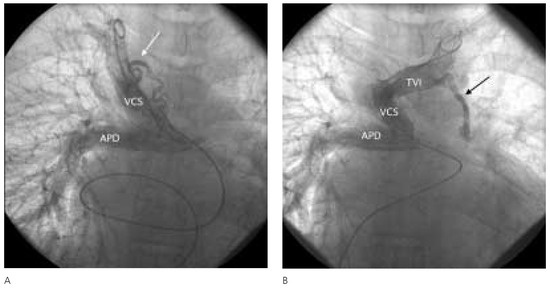

Collatérales Veineuses Systémiques Après Dérivation Cavo-Pulmonaire Totale

by Pedro Trigo Trindade, Dominique Didier, Beat Friedli, Maurice Beghetti and Yacine Aggoun

Cardiovasc. Med. 2005, 8(5), 207; https://doi.org/10.4414/cvm.2005.01101 - 27 May 2005

Viewed by 102

Abstract

Une patiente de 18 ans, élève-infirmière, connue pour une cardiopathie congénitale [...] Full article

Show Figures

Figure 1